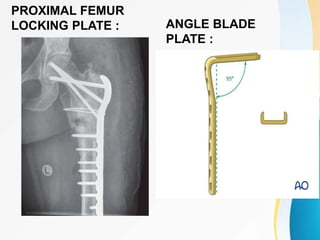

PROXIMAL FEMUR

LOCKING PLATE : ANGLE BLADE

PLATE :

PROXIMAL FEMUR LOCKING PLATE: ANGLE BLADE PLATE :